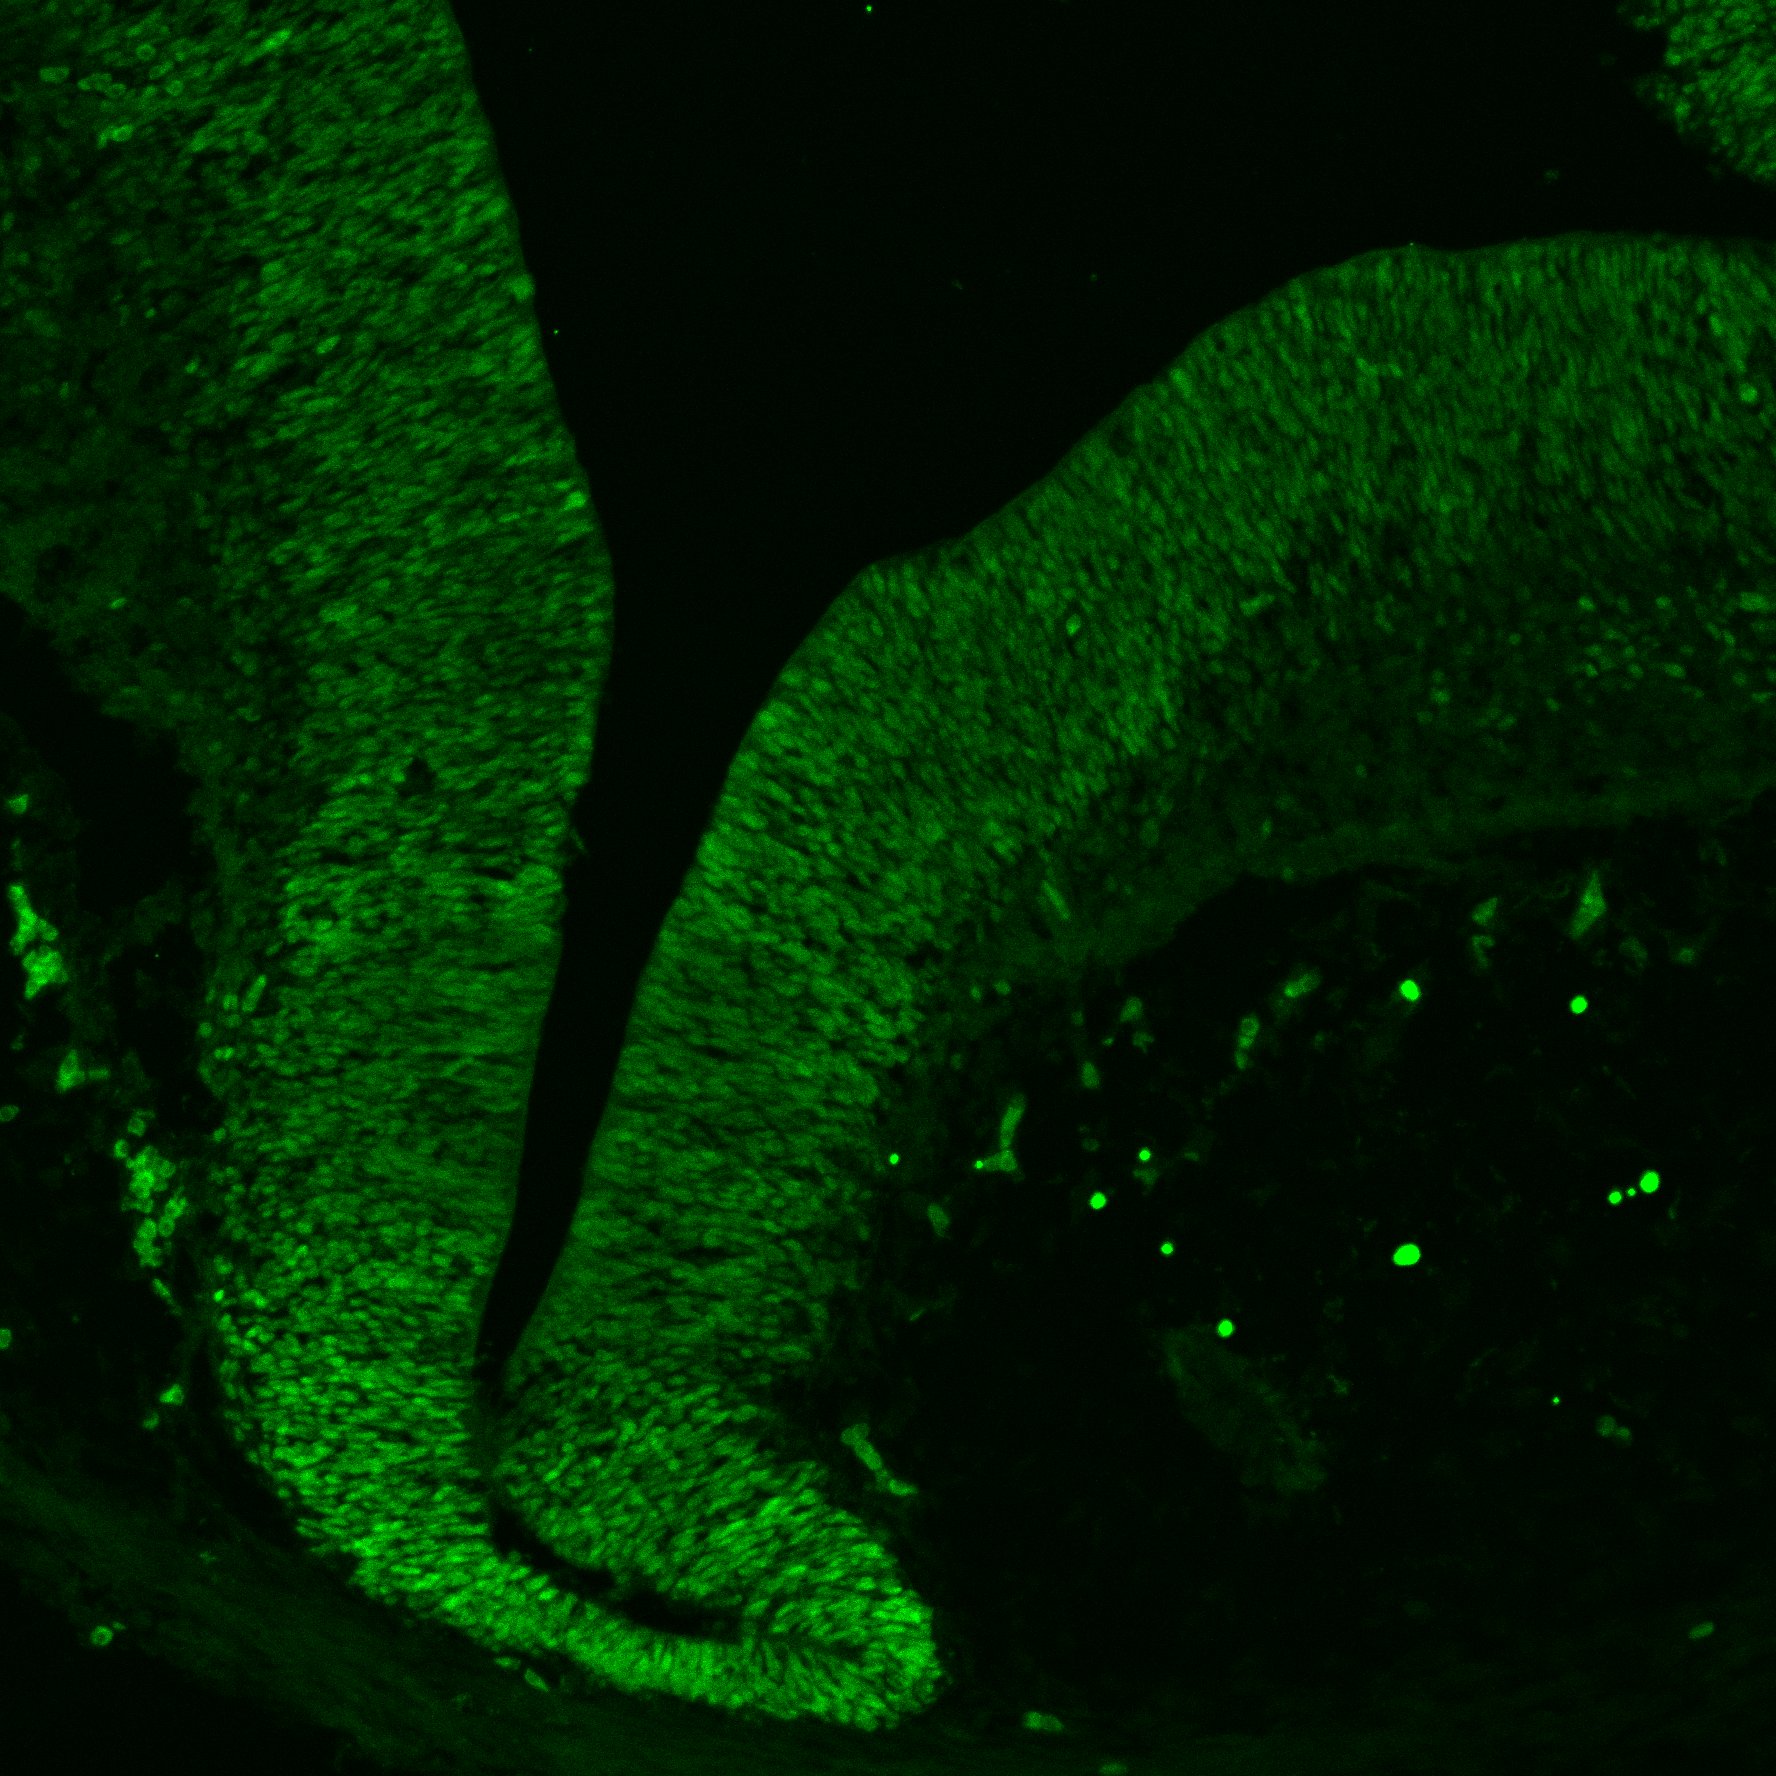

An anatomical analysis of the developing human midbrain from 6 post-conceptional weeks (PCW) to 22 PCW reveals increased tissue complexity, characterized by the emergence of dopaminergic nuclei, as highlighted by immunofluorescence analysis for tyrosine hydroxylase (TH).

MAP2

11PCW human midbrain

13PCW human midbrain

15PCW human midbrain

17PCW human midbrain

19PCW human midbrain

22PCW human midbrain